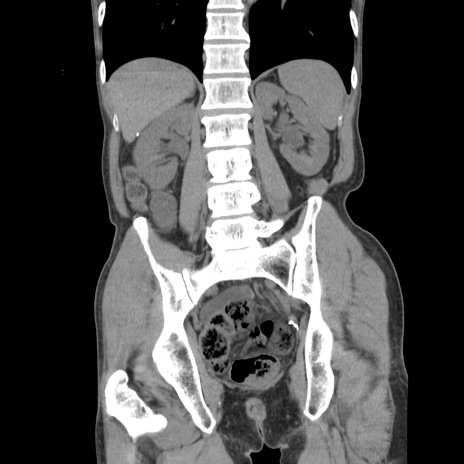

症例11(冠状断像)

【症例】 60歳代男性

【主訴】 下腹部痛

【現病歴】 本日夜中より下腹部痛の症状認め、受診。

【既往歴】 膀胱癌(膀胱全摘+尿管皮膚瘻術) 、胃癌術後

【身体所見】 BT 35.3℃、PR 58/min、BP 136/98mHg、腹部平坦、軟、腸蠕動音±、ストマ留置あり、左上腹部~正中部に圧痛あり、反跳痛なし。

【データ】WBC 5100、CRP0.01